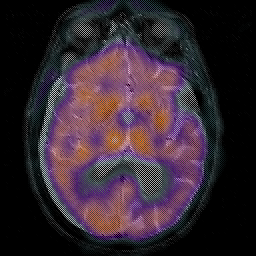

Subdural Hygroma,overlay -- Slice #24